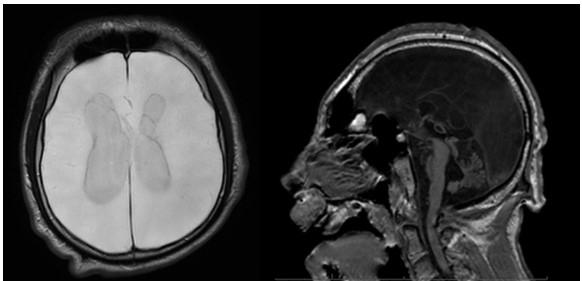

An MRI of the brain shows diffuse encephalomalacia involving the supratentorial brain parenchyma with volume loss of the cerebellum, the pons, and brain stem. (Figure 1)